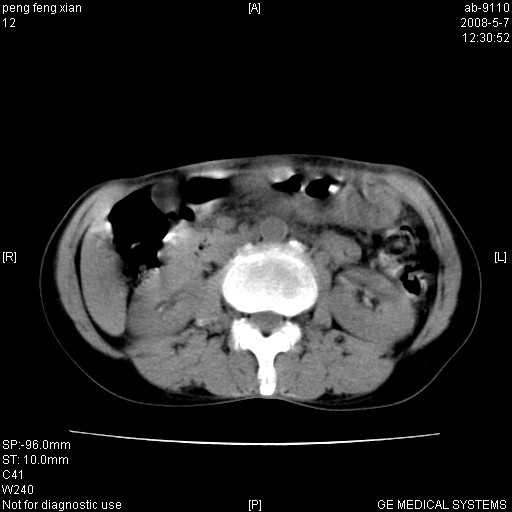

女,56岁。b超左一腹包块,考虑胃肠道肿瘤。

胃壁增厚,左前胸壁局限性隆起,考虑胃癌可能性大,建议做胃镜

典型胃癌胰体尾部受侵。

胃体部胃壁增厚,不均匀性强化,与胰腺分解欠情.

考虑:胃癌,胰腺受侵待除外.

鉴别:胃淋巴瘤(强化不明显)

建议:胃镜检查.